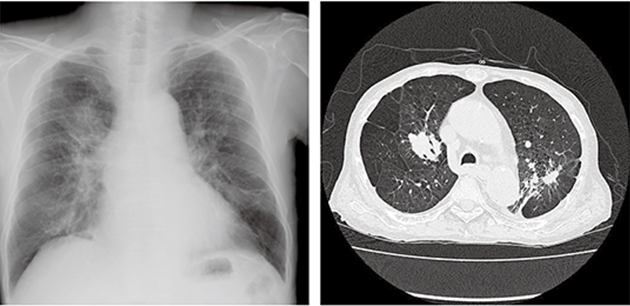

粉塵沉積的肺部X光造影(圖片來自網(wǎng)絡(luò))

具體來說,當(dāng)粉塵顆粒進(jìn)入肺泡內(nèi)部或者間隔時(shí),雖然大部分可以通過呼吸作用被排出體外,仍有小部分吸附、沉積下來,最終對(duì)肺部造成以下幾種可能的潛在惡劣影響:

一般檢查以X射線為主,并結(jié)合患者職業(yè)情況予以判斷。根據(jù)診斷標(biāo)準(zhǔn),塵肺病一般不難確診。但有時(shí)候小孩子長期跟父母生活在煤場或者發(fā)電廠等嚴(yán)重大氣污染的地區(qū),因?yàn)椴]有直接從事相關(guān)工作,在診斷的時(shí)候容易被誤診為肺結(jié)核。